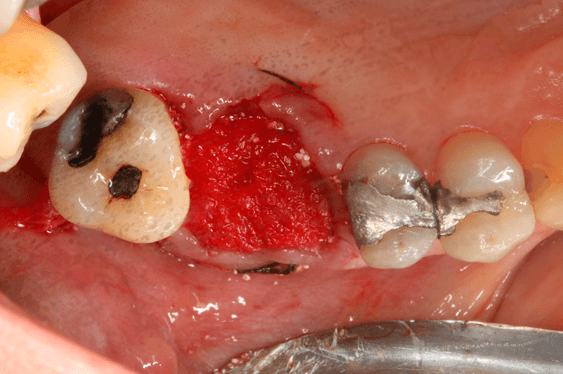

Avaliamos o desempenho do biomaterial de hidroxiapatita com colágeno tipo I (Extra Graft XG-13®) na manutenção do volume alveolar.

A aplicação como o caso clínico abaixo se mostrou uma técnica acessível a todos cirurgiões dentistas, pois se trata de um procedimento de simples execução e acessível. Logo, deveria constar na clínica diária.